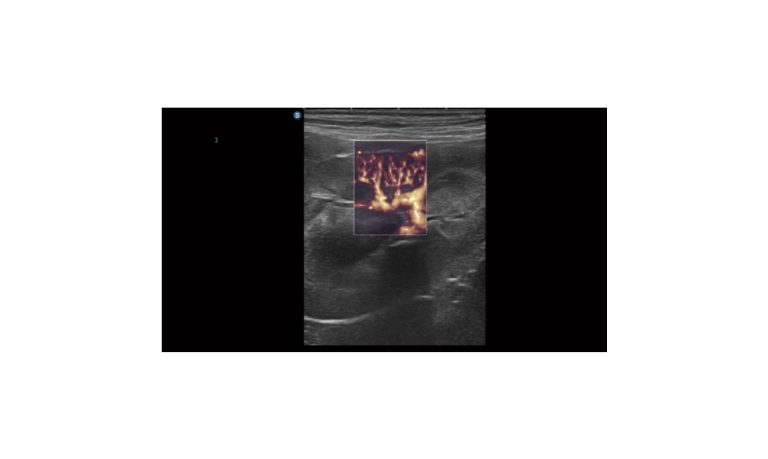

Ultrasound

Wide range of Ultrasound machines that suites a variety of applications from abdominal to rectal scans, we take in consideration how the world is moving towards mobility and mobile applications.

SonoScape Pro Pet E11

Smart Imaging

Introducing the first portable ultrasound with the C-Field+TM platform, redefining diagnostic imaging. Designed for veterinarians, it delivers unmatched clarity, ultra-fast processing, and seamless adaptability for all species. Experience Smart Imaging, Heartfelt Care—anywhere.

Equipped with cutting-edge veterinary software and optimized workflows, it embodies our commitment to Smart Imaging, Heartfelt Care – Wherever Their Journey Leads, with unparalleled performance and adaptability, this innovative system empowers veterinarians to provide exceptional care across all diagnostic applications,

EBIT50/60 VET

All the power you need

The EBit provides all the power you need for today´s challenging clinical environment, yet remain ultra-portable, ultra-affordable. With its cutting-edge imaging technologies, precise and intuitive workflow, ergonomic and eco-friendly design, versatile transducers for all applications from top to toe, we firmly believe the EBit to be the very best portable ultrasound in its class today.

ECO5 VET

Ultra-Portable, Ultra- Affordable, Color doppler

The multi-purpose user presets, comprehensive measurement & report system, built-in EasyView image achieve system, quick image storage / retrieve / transfer, one-button direct print, make the complete workflow better than what you can dream of.